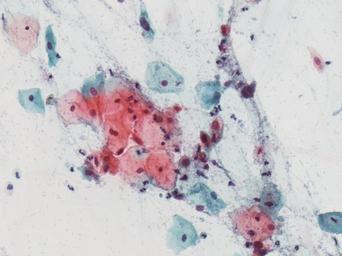

| Keywords: lesión intraepitelial escamosa de bajo grado lesiónintraepitelialescamosadebajogrado citología de cuello uterino citologíadecuellouterino citología exfoliativa ginecológica citologíaexfoliativaginecológica citología de cribado citologíadecribado citología anatomía patológica anatomíapatológica bethesda 2001 bethesda2001 osuna cérvix uterino cérvixuterino hpv españa screening lsil enfermedades de transmisión sexual enfermedadesdetransmisiónsexual imágenes de citología ginecológica imágenesdecitologíaginecológica papanicolaou test de papanicolaou testdepapanicolaou tinción de papanicolaou tincióndepapanicolaou drawing Células con núcleo y citoplasma aumentado de tamaño, núcleos irregulares, como plumosos, tendencia al color naranja de muchas células, halos en algunos casos, núcleos dobles en otros, algunos núcleos hipercromáticos. Células con núcleo y citoplasma aumentado de tamaño, núcleos irregulares, como plumosos, tendencia al color naranja de muchas células, halos en algunos casos, núcleos dobles en otros, algunos núcleos hipercromáticos. |